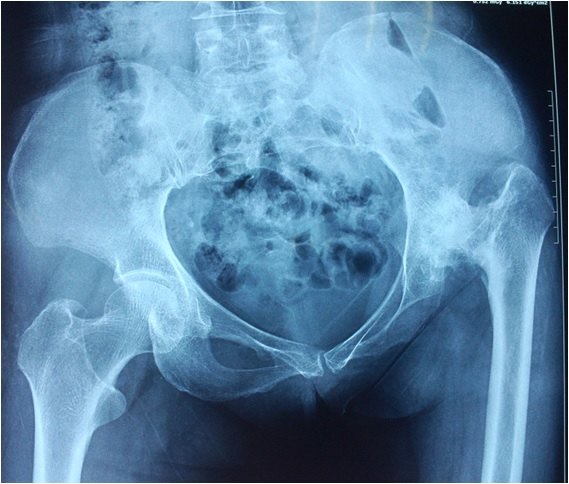

术前x线可见患者双膝内翻畸形严重,膝关节内外侧磨损不一.

严重的双膝关节内翻畸形.